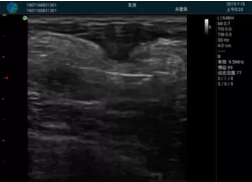

M20查看:囊內(nèi)回聲均勻,邊界清晰,囊壁光滑

M20引導(dǎo)抽吸術(shù)后囊腫消失,原區(qū)域空腔形成,脂肪層與腺體層架構(gòu)發(fā)生改變